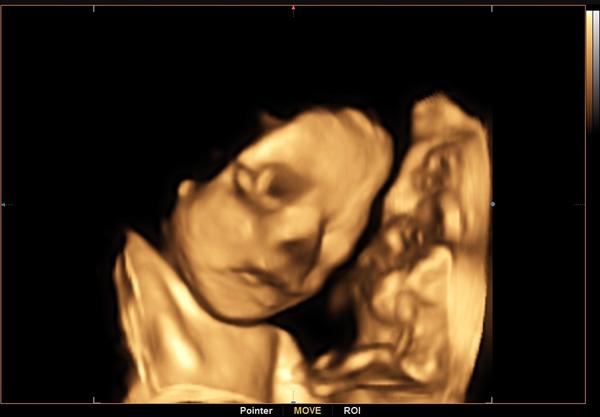

Holky tak mame po utz🙂 obe jsme zdrave🙂 za 4 tydny velky posledni ultrazvuk ❤️Uz si ji chci pochovat